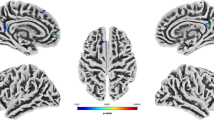

Only one sub-scale of the trait aggression scales correlated significantly with the offenders GMV. RPQ reactive aggression was negatively linked with GMV in the right middle and superior temporal gyrus (Table 3, Fig. 1a). No other sub-scales of the AQ, RPQ and PCL-R correlated significantly with the GMV of offenders.

Negative correlations of gray matter volume (GMV) with aggression and psychopathy in offenders. a Negative correlations resulting from whole brain multiple regression analyses at p = 0.001 level with a cluster-defining threshold of p(uncorrected) < 0.05 of GMV with antisocial behavior (PCL-R) reactive aggression (RPQ) in offenders, implementing total intracranial volume (TIV) and age as covariates. b Illustration of cluster emerging from the overlap of both results (RPQ reactive aggression × GMV and PCL-R antisocial behavior (facet 4) × GMV) comprising the right middle temporal gyrus. c Partial correlations of offenders individual GMV within the overlap cluster and PCL-R facet 4 (antisocial behavior) and RPQ reactive aggression scores revealed negative association of overlap cluster values with reactive aggression and antisocial behavior in offenders (controlled for TIV and age), ***p < 0.001

Overlap of brain structure correlates of reactive aggression and antisocial behavior

One region in the right temporal cortex emerged in two in separate analyses. To identify the overlap, the results from the regression analyses of RPQ reactive aggression × GMV and PCL-R antisocial behavior (facet 4) × GMV were transformed into one unified MNI space and the MANGO function “create logical overlays” (Research Imaging Institue, UTHSCSA, 2018) was used. One cluster (952 mm3) in the right middle temporal gyrus (center of gravity x y z: 50 − 28 − 3) was found to be negatively correlated with both measures (Fig. 1b).